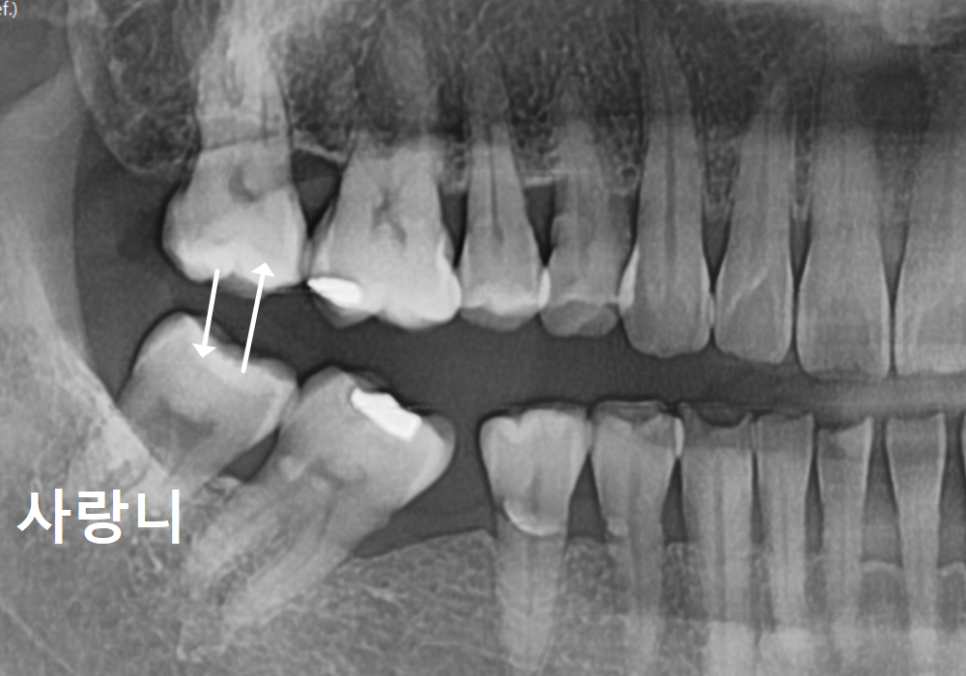

오른쪽 아래(#46)와 왼쪽 아래 맨 끝(#37)

치아를 발치한 지 꽤 오래된 상태였죠.

| 1) 오른쪽 어금니#47,48 어금니들이 빈 곳으로 많이 쏠려 #46 상실 부위에 임플란트를 심을 공간이 부족한 상태2) 왼쪽 어금니위쪽 어금니(#27)가 맞물릴 곳이 없어 아래로 정출되어 내려온 상태 |